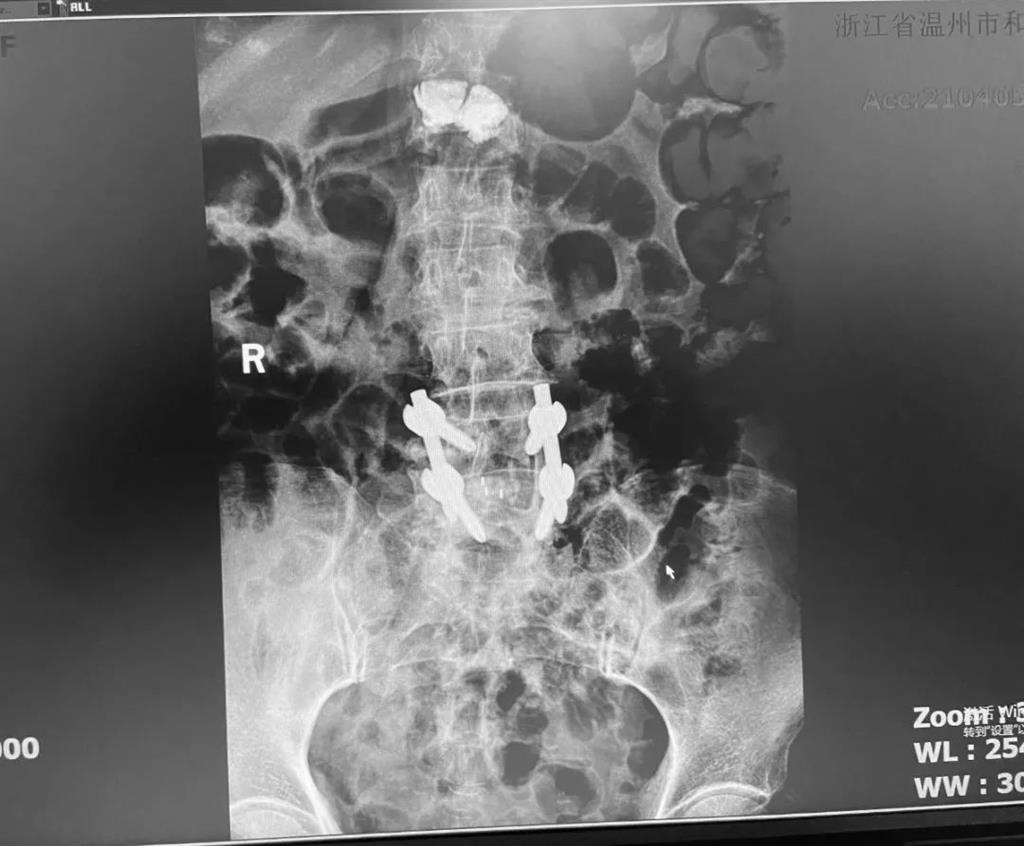

據(jù)了解,脊柱內(nèi)鏡下腰椎融合術(shù)只需要打幾個“鑰匙孔”即可完成。聽起來是不是很簡單?在脊柱內(nèi)鏡下,劉丹主任先后為患者進(jìn)行了椎管減壓、椎間盤摘除,再實施椎弓根螺釘放置、椎體植骨融合內(nèi)固定,一系列步驟有條不紊。

看似簡單的幾個步驟,但實際上很復(fù)雜,需要主刀醫(yī)生有豐富的手術(shù)經(jīng)驗和細(xì)致耐心的操作。

劉丹主任表示,傳統(tǒng)手術(shù)需要廣泛剝離脊椎兩側(cè)的肌肉,術(shù)后容易產(chǎn)生疤痕、肌肉萎縮、腰部疼痛等;術(shù)中出血多,往往需要額外輸血,另外創(chuàng)傷大的同時也容易破壞脊椎的正常結(jié)構(gòu),對于老年人、體弱的人群來講,恢復(fù)期長、風(fēng)險多。

而脊柱內(nèi)鏡下腰椎融合術(shù),作為目前國內(nèi)脊柱微創(chuàng)領(lǐng)域大力發(fā)展的新技術(shù),徹底改變了傳統(tǒng)開刀椎板切除椎間植骨融合內(nèi)固定的大創(chuàng)傷現(xiàn)狀,可以在較大程度上減少對脊柱后方穩(wěn)定結(jié)構(gòu)的破壞,創(chuàng)傷小,出血少,術(shù)后恢復(fù)快。

非常適用于體質(zhì)較差不能耐受開放手術(shù)的老年患者,且手術(shù)全程均在內(nèi)鏡監(jiān)測下進(jìn)行,能夠最大程度地避免硬膜囊和神經(jīng)根損傷,手術(shù)安全性更高。

術(shù)中只需切開4個如“鑰匙孔”般大小的孔道